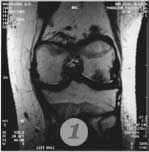

Пример №4 Магнитная томография (МРТ) помогает произвести диагностику сустава до операции

3. повреждение мениска на МРТ